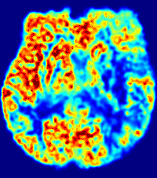

For a better insight into an estimated velocity field 𝐕𝐕{\bf{V}} and diffusion field 𝐃𝐃{\bf{D}}, we compute the following maps: (1) 𝐕rgbsubscript𝐕𝑟𝑔𝑏{\bf{V}}_{rgb}: Color-coded orientation map of 𝐕=(Vx,Vy,Vz)T𝐕superscriptsuperscript𝑉𝑥superscript𝑉𝑦superscript𝑉𝑧𝑇{\bf{V}}=(V^{x},V^{y},V^{z})^{T}, obtained by normalizing 𝐕𝐕{\bf{V}} to unit length and mapping its 3 components to red, green, blue respectively; (2) 𝐕2subscriptnorm𝐕2\|{\bf{V}}\|_{2}: 222 norm of 𝐕𝐕{\bf{V}}; (3) D𝐷D: scalar field in Eq. 5.

Fig. 3 and Fig. 4 show the PIANO feature maps estimated from two ISLES 2017 patients: all are highly consistent with the lesion in both cases. Details of the blood flow trajectories are revealed in 𝐕rgbsubscript𝐕𝑟𝑔𝑏{\bf{V}}_{rgb} by the ridged patterns and the sharp changes of colors in the unaffected (right) hemisphere, while the flat patterns appearing within the lesion provide little directional information about the velocity and indicate low velocity magnitudes. Velocity magnitudes are more directly visualized via 𝐕2subscriptnorm𝐕2\|{\bf{V}}\|_{2}, from which one can easily locate the lesion where 𝐕2subscriptnorm𝐕2\|{\bf{V}}\|_{2} is low. D𝐷D also indicates lower diffusion values in the lesion, though with less contrast potentially due to the fact that it captures the accumulated effect of CA diffusion at the voxel-level.

To better illustrate the prediction accuracy, and therefore the estimation accuracy of 𝐕𝐕{\bf V} and D𝐷{D}, of PIANO, we provide the corresponding predicted time-series of CA concentration images in Fig. 5 and Fig. 6 for the same patients in Fig. 3 and Fig. 4, respectively. We see that PIANO is capable of predicting the CA concentration given their initial state, indicating its ability to successfully capture 𝐕𝐕{\bf V} and D𝐷{D}. Note that although the concentration values for these two patients differ considerably, caused by the different total volume of injected CA, PIANO is still able to provide plausible estimates.